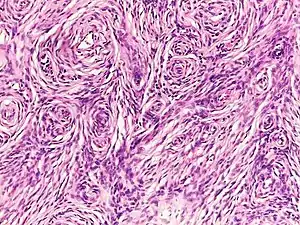

- Histopathology of neurofibroma: A spindle cell lesion composed of slender fibroblast-like cells with storiform pattern and very low amount of stroma.[16]